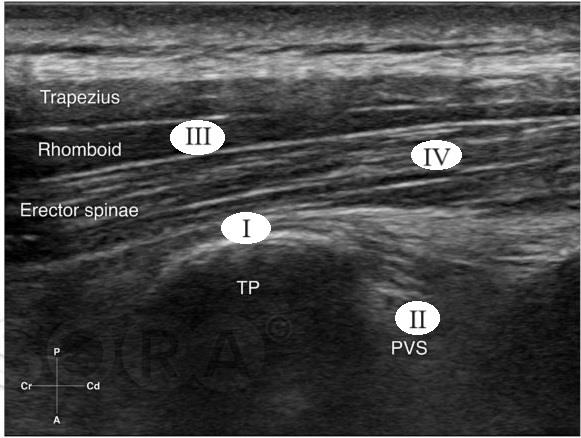

A imagem sonográfica a seguir corresponde a um bloqueio do plano do eretor da espinha, do inglês the erector spinae plane block ou, simplesmente, ESPBlock, classicamente descrito ao nível de T5, que faz parte do arsenal terapêutico do anestesiologista.

Legenda: TP – Processo Transverso; PVS – Espaço Paravertebral.

Considerando a figura, o local correto de administração do anestésico, nessa abordagem, e os músculos que compõem a musculatura eretora da espinha, ao nível do tórax, respectivamente, são: